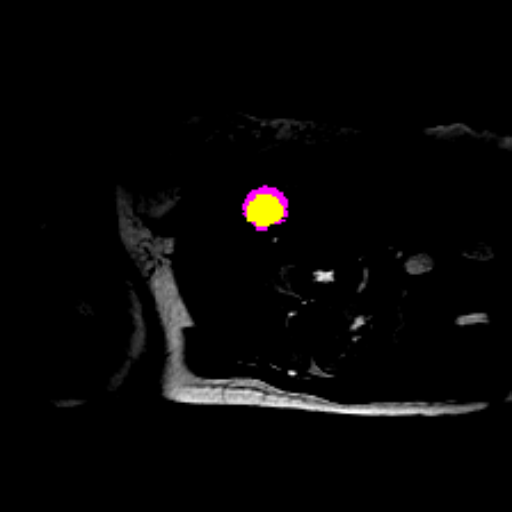

Figure 3 presents a qualitative comparison of segmentation performance on examples from the Synapse, BTCV, ACDC, and ISIC17 datasets. The first two examples (from Synapse) highlight variations in segmentation performance among U-Net, TransUnet, Mamba-Unet, and Swin-Unet. While Swin-Unet performs well in the first example, its performance decreases in the second example, particularly in segmenting the organ highlighted in blue. Additionally, it misclassifies background regions as the class highlighted in orange. In contrast, our approach demonstrates high robustness in segmenting all classes accurately and aligning well with the ground truth masks.

Across BTCV, ACDC, and ISIC17, the comparison methods exhibit varying performance depending on the task and class. For instance, Mamba-Unet struggles to segment multiple organs in BTCV, even misclassifying certain classes as others. In the ACDC dataset, both TransUnet and Mamba-Unet perform poorly in segmenting the three classes. In the last column (ISIC17), Swin-Unet oversegments the skin lesion compared to the ground truth. Unlike the comparison models, our approach consistently delivers effective segmentation across different tasks and datasets.

These qualitative findings further reinforce the quantitative results presented in the experimental section, demonstrating the effectiveness of our MambaCAFU model in handling binary and multi-class segmentation across diverse medical imaging modalities and tasks.

Slice GT Unet TransUnet Mamba-Unet Swin-UMamba MambaCAFU-V1

Figure 3: Visual comparison of segmentation examples from Synapse (first two examples), BTCV (3-4 examples), ACDC (5th example) and ISIC17 (last example). Columns: input slice, ground truth, Unet, TransUnet, Mamba-Unet, Swin-UMamba, and MambaCAFU-V1.